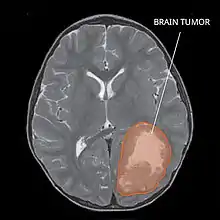

Magnetic resonance image of PNET

Several analysis can be used to determine the presence of the disease. Physical examinations showing papilledema, visual field defects, cranial nerves palsy, dysphasia, and focal neurological deficits are evidences for possible tumor.[2] PNETs can also be spotted through computed tomography (CT) and magnetic resonance imaging (MRI).[2] In images produced by MRIs, an irregular augmentation among a solid mass will indicated the presence of tumor.[3] However, the results of MRIs are usually ambiguous in defining the presence for this specific tumor.[2] In CT scans, the presence of PNETs will be indicated by an elevated density and an increase in volume of the brain.[2] The CT scan can also show calcification,[3] which is present in 41-44% of PNET cases.[2] Since the tumor can be replicated in other parts of the nervous system through the cerebrospinal fluid (CSF), a CSF analysis can also be conducted.[2] A spinal MRI is a fourth type of analysis that is useful in investigating the level of tumor propagation to the spinal cord.[2]